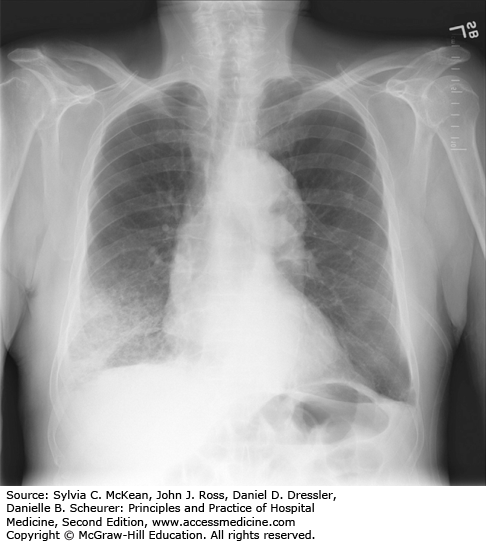

Pneumococcal lobar pneumonia. A 78-year-old man with chronic lung disease had subjective fever, right-sided pleuritic chest pain, and greatly increased shortness of breath for 2 days. He was afebrile, and his WBC count was 10,600/mm3 with 40% band forms. Blood cultures were positive for S. pneumoniae. A sputum submitted for culture more than 24 hours after antibiotics were begun yielded no pneumococci.